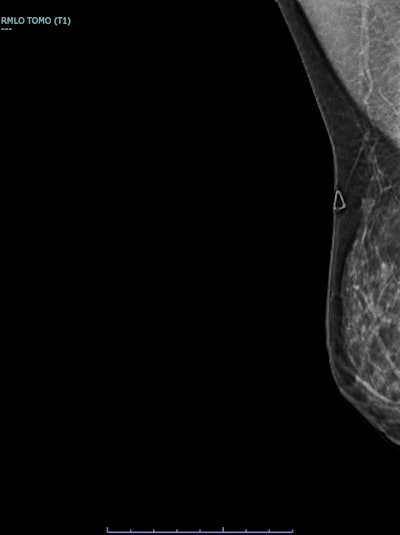

Correlative tomosynthesis, sonographic, and histopathological findings in a 45-year-old woman presenting with a palpable right breast lump. Synthesized 2D mammogram, right breast, mediolateral oblique (MLO) projection. No discrete abnormality is visualized due to extremely dense parenchyma (BI-RADS category D). A retroglandular silicone breast implant is in situ.

3D breast tomosynthesis, right breast, MLO push-back view of the same patient. Localized increased stromal density corresponding to the clinically palpable lump, more evident compared with routine 2D projections.